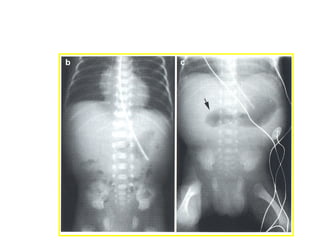

Signo del "remolino"(flecha).

OI secundaria a cáncer de colon ascendente (flecha blanca)

con dilatación de ciego (flecha negra)

e intestino delgado por incompetencia de válvula ileocecal.

OI secundaria a hernia externa

Cálculo impactado en íleon (flecha).

OI secundaria a enfermedad de Crohn

que compromete el íleon distal (flecha).

• 34.

Signo del "remolino"(flecha). OIsecundaria a cáncer de colon ascendente (flecha blanca) con dilatación de ciego (flecha negra) e intestino delgado por incompetencia de válvula ileocecal.

• 35.

OI secundaria ahernia externa Cálculo impactado en íleon (flecha).

• 36.

OI secundaria aenfermedad de Crohn que compromete el íleon distal (flecha).